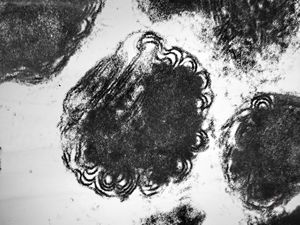

M,15y. | megamitochondria with lamellar inclusions in hepatocyte - Wilson disease